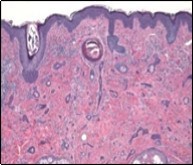

Lesions are generally superficial and infrequently invade lower dermis. Tendency for peri-neural or intra-neural infiltration, cogitated in adjunctive cutaneous carcinomas, is exceptional in desmoplastic trichoepithelioma. Nevertheless, desmoplastic trichoepithelioma can be exemplified as a component of particularly desmoplastic, cutaneous carcinomas demonstrating foci of peri-neural involvement 4, 5. Figure 1, Figure 2, Figure 3, Figure 4, Figure 5, Figure 6, Figure 7, Figure 8.

Figure 6.Desmoplastic trichoepithelioma displaying few horn cysts, nests of basaloid cells and an abundance of desmoplastic, fibrotic stroma with an attenuated squamous epithelial lining 13.